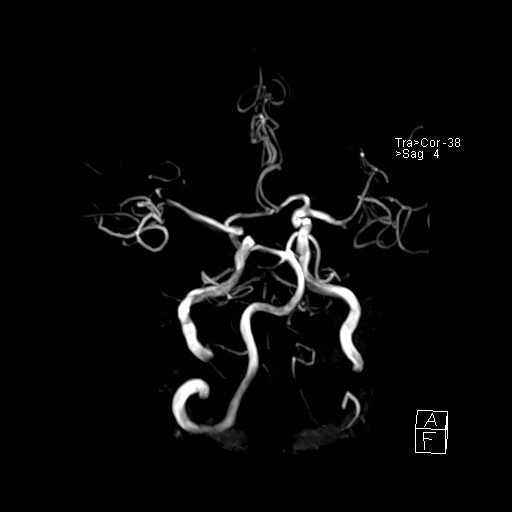

239716 - VILLANUEVA, WILLIAM A. - Number 3 |

239716 - VILLANUEVA, WILLIAM A. - Number 3 |